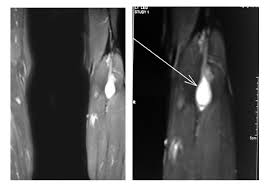

Surgeons carefully remove your schwannoma while taking care to preserve nerve fascicles that arent affected by your tumor. Rarely nerve sheath tumors can be malignant. On conventional MRI and diffusion-weighted imaging DWI MPNSTs and BPNSTs showed significant differences in tumor size margin presence of perilesional edema and absence of split fat fascicular.

On conventional MRI and diffusion-weighted imaging DWI MPNSTs and BPNSTs showed significant differences in tumor size margin presence of perilesional edema and absence of split fat. View chapter Purchase book.

Sciatic Nerve Schwannoma A Rare Case

Results of this limited experience indicate linear acceleratorbased spinal radiosurgery is feasible for treatment of benign nerve sheath tumors. Most benign nerve sheath tumors need no treatment other than observation which involves following up with repeat physical examinations and serial imaging. This of course means that surgery is required. On conventional MRI and diffusion-weighted imaging DWI MPNSTs and BPNSTs showed significant differences in tumor size margin presence of perilesional edema and absence of split fat fascicular. Some nerve sheath tumors are treated with surgery. On conventional MRI and diffusion-weighted imaging DWI MPNSTs and BPNSTs showed significant differences in tumor size margin presence of perilesional edema and absence of split fat. Rarely nerve sheath tumors can be malignant.